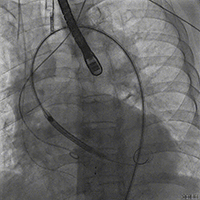

瓣膜释放

释放后造影

在释放过程中,手术团队严密监控各项体征,经充分评估后完全释放瓣膜。释放后评估未见冠脉阻挡,无传导阻滞,无瓣周返流,跨瓣压差由术前的160 mmHg降至10mmHg,血流动力学稳定。出导管室前即拔除气管插管,患者后自诉症状明显改善。手术获得圆满成功。